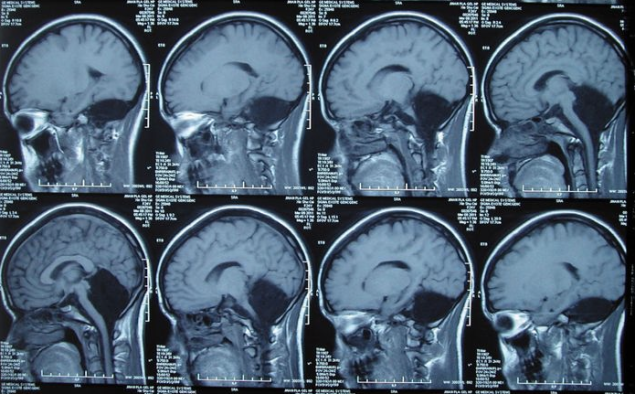

La revista científica 'Brain' ha revelado el caso de una paciente de 24 años y nacionalidad china que ha vivido toda su vida sin cerebelo. La mujer se sometió a estudios médicos debido a los mareos y vomitos que sufría desde hacía tiempo.

Los exámenes descubrieron que carecía de cerebelo, una región del cerebro que supuestamente es imprescindible para el buen funcionamiento del mismo. Se trata de un caso con muy pocos precedentes ya que normalmente los niños que sufren esta alteración no llegan a alcanzar la edad adulta. Esta mujer no sólo ha conseguido cumplir 24 años, sino que se ha convertido en madre y apenas ha sufrido transtornos asociados a la ausencia de cerebelo.